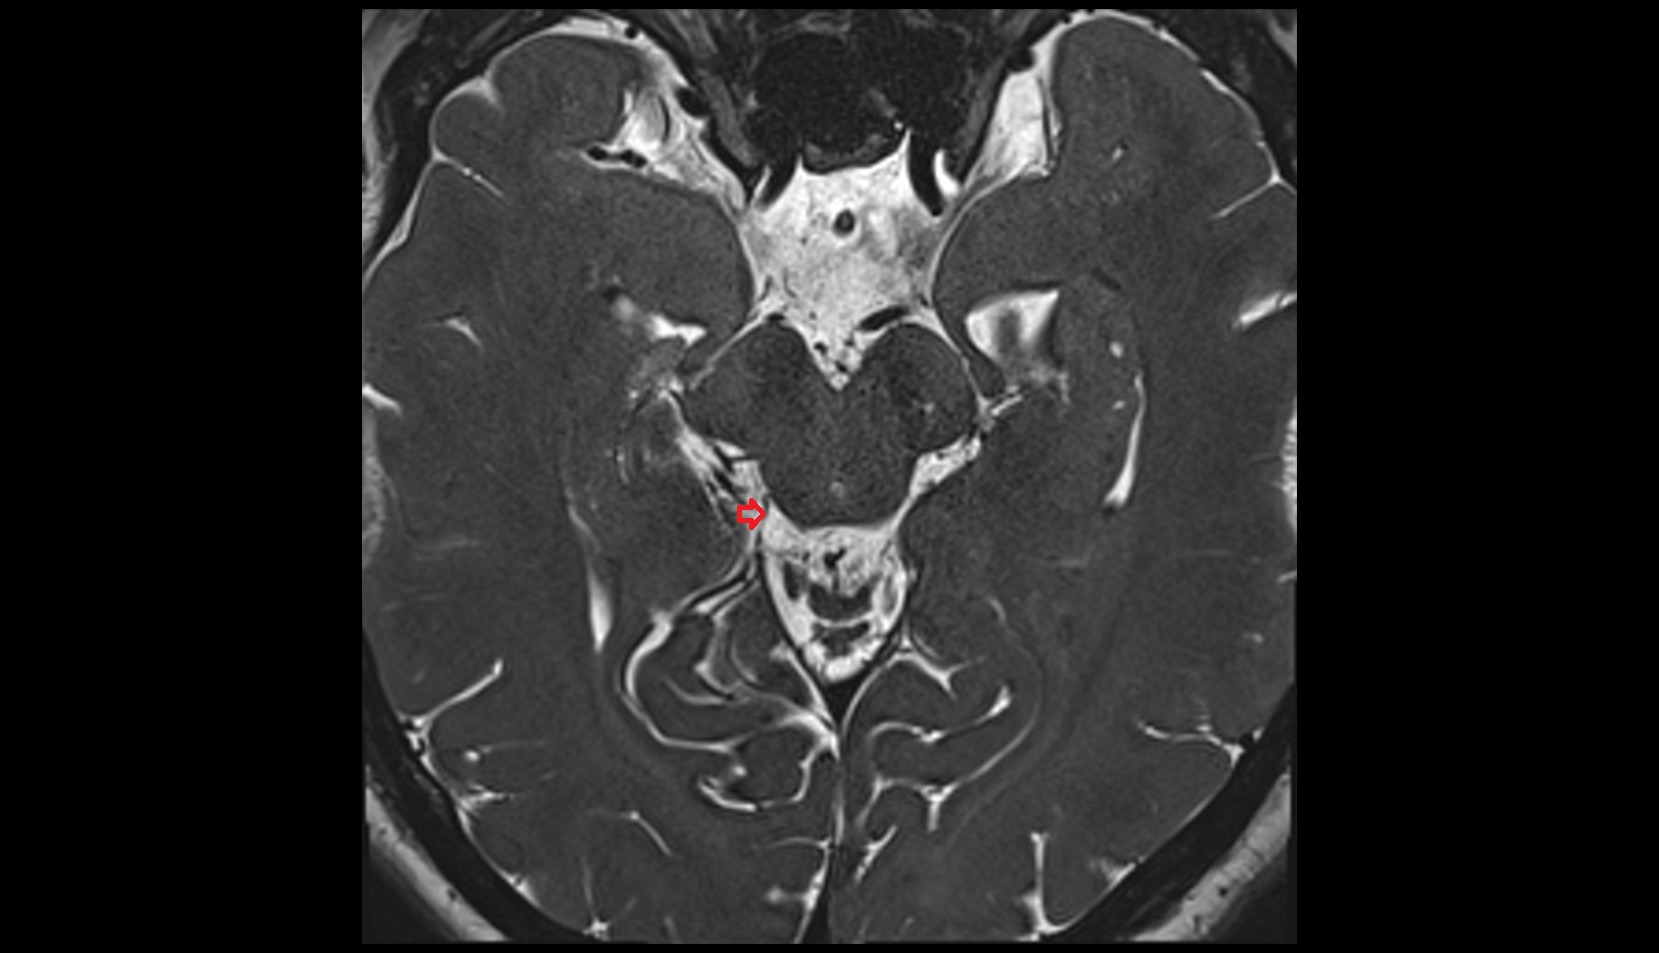

- Lateral aperture of fourth ventricle (foramen of Luschka)